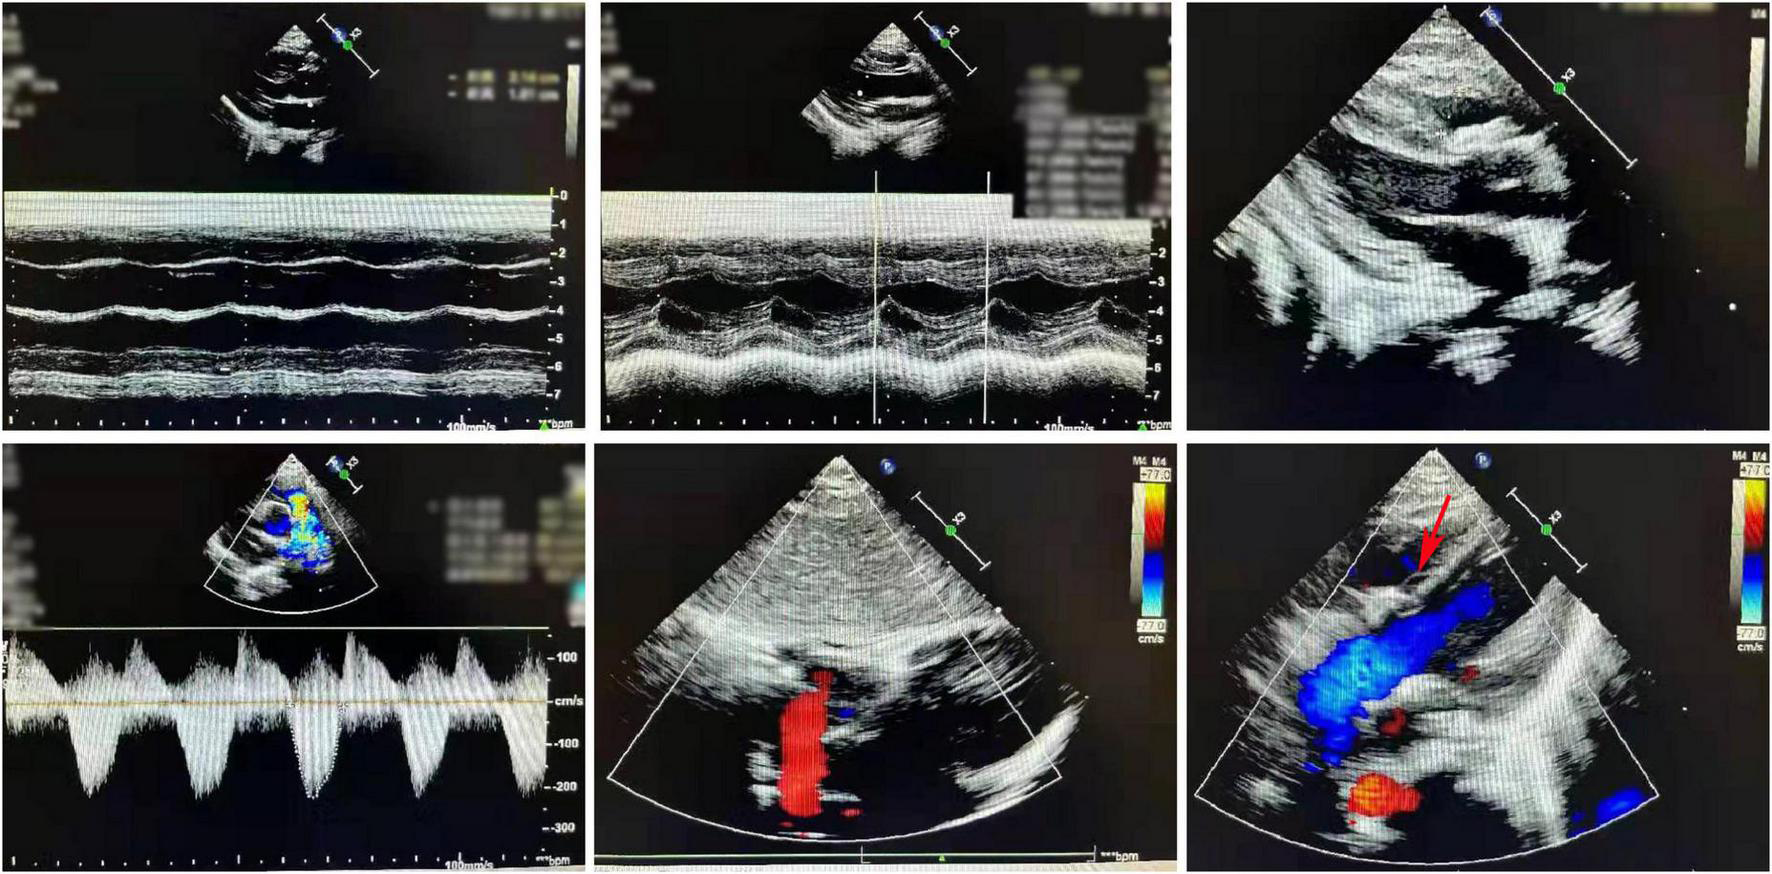

Cardiac ultrasound characteristics

The postoperative cardiac ultrasound (Figure 2) showed that the inner diameter of the cardiac cavities was within the normal range. However, the motion amplitude of the ventricular septum was reduced. The ventricular septum and the left ventricular posterior wall were not thick. The left ventricular posterior wall showed normal motion. The atrial septum was continuous and complete. A strong patch echo was observed around the ventricular septum. The surrounding tissues did not show any obvious cracks. The morphological structure and the opening and closing movements of the valves were normal. The right ventricular outflow tract was not obstructed. A hypertrophic muscle bundle was not detected. The inner diameter of the pulmonary artery was normal (Figure 2). Doppler examination did not detect any shunt signal at the systolic ventricular level. The peak forward flow velocity of the pulmonary artery flow was 2.2 m/s (Figure 2).

FIGURE 2

A representative image of the cardiac ultrasound (postoperative) shows the normal internal diameter of each chamber, low septal motion amplitude, and strong plaque echoes around the septum. The right ventricular outflow tract is not obstructed. The muscle bundles are not hypertrophic. The internal diameter of the pulmonary artery was normal.